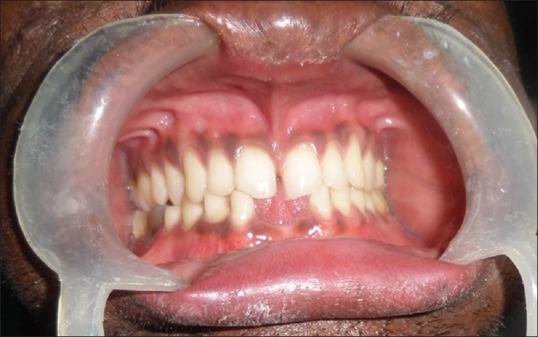

Pachyonychia congenita is a rare type of ectodermal dysplasia further classified into 4 types. Cutaneous manifestations seen in most of the cases of Pachyonychia congenita include palmoplantar keratoderma, follicular hyperkeratosis, wedge shaped nails, oral leukokeratosis and woolly hair. A 25-year-old male presented to us with thickened nails and scanty scalp hair. On examination, we noticed hyperkeratotic plaques over both the soles, palmoplantar hyperhidrosis and yellowish discoloration, wedging with subungual hyperkeratosis of all the nails. Follicular hyperkeratotic papules and steatocystoma multiplex were also observed over the scalp and face. The patient had history of natal teeth and on dental examination, lower central incisors were absent. All cutaneous changes in our case had manifested first in the 2(nd) decade except for natal teeth. All the above features suggested the diagnosis of pachyonychia congenita with late onset (PC tarda), which is an infrequently reported rare variant.

先天性厚甲症是一种罕见的外胚层发育不良类型,进一步分为4种类型。大多数先天性厚甲症病例的皮肤表现包括掌跖角化病、毛囊角化过度、楔形甲、口腔黏膜白斑和羊毛状发。一名25岁男性前来就诊,其指甲增厚且头皮毛发稀少。检查时,我们注意到双足底有角化过度斑块、掌跖多汗和发黄变色,所有指甲均有楔形甲伴甲下角化过度。头皮和面部也观察到毛囊角化过度丘疹和多发性皮脂囊肿。该患者有诞生牙病史,牙科检查发现下颌中切牙缺失。除诞生牙外,本例所有皮肤改变均在第二个十年首次出现。上述所有特征提示诊断为迟发性先天性厚甲症(PC tarda),这是一种罕见且报道较少的变异型。